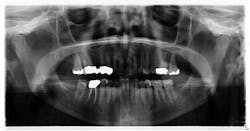

Patient: 74-year-old female

- 5 x 0.5-inch radiopaque mass on the left side, just anterior to the angle of the mandible

- Area is asymptomatic upon palpation

- Lesion has been present for at least six years